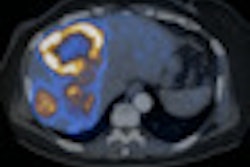

![]() |

| Patient with oral cancer shows very high values for rBF, rBV, and PS; lymph node was found to be malignant at histology. |